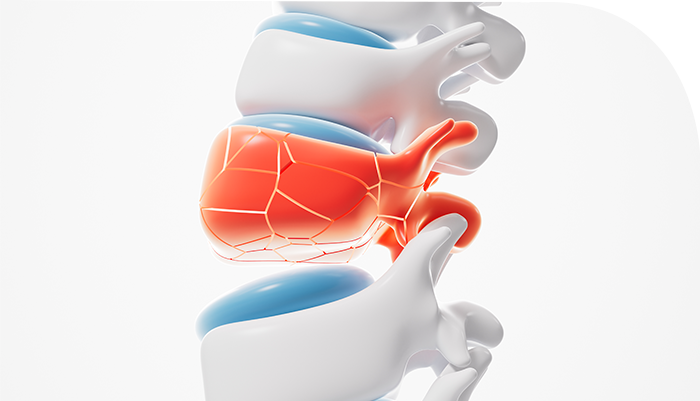

°¨¿°¿¡ Ãë¾àÇÑ »óÅ·ΠÀÀ±Þóġ ¹× ±ä±Þ ¼ö¼úÀÌ ÇÊ¿äÇÑ °æ¿ì°¡ ¸¹½À´Ï´Ù.

°ñÀý ºÎÀ§°¡ ÇǺΠ¹ÛÀ¸·Î µ¹ÃâÇϰųª »À°¡ ºÎ·¯Á®´Ù¸¥ ½Åü Á¶Á÷ÀÇ ¼Õ»óÀ» °âÇϰí ÀÖ´Â »óŸ¦ ¸»ÇÕ´Ï´Ù.

Á÷Á¢ÀûÀΠŸ°Ý, ±³Åë»ç°í·Î ÀÎÇÑ Ãæµ¹, ³«»ó»ç°í·Î ¿Ü»óÀ» ÀÔ¾úÀ» °æ¿ì µî »À¿¡ °¡ÇØÁø ½ÉÇÑ Ãæ°ÝÀ¸·Î ÀÎÇØ ¹ß»ýÇϸç, Ãʱ⿡´Â Æó¼â¼º °ñÀýÀ̾ú´Ù°¡ ÁÖÀ§ ÇǺÎÁ¶Á÷¿¡ ±äÀåÀÌ ¸¹¾ÆÁ®¼­ °³¹æ¼ºÀ¸·Î ¹Ù²ð ¼ö ÀÖ½À´Ï´Ù.